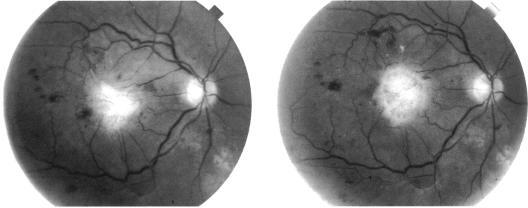

A case of a macular idiopathic choriovitreal membrane is described which developed in a diabetic man. On initial examination the patient was found to have a pigment epithelial detachment with a choroidal neovascular membrane (CNVM) in the right eye. Two months after the first visit the CNVM was seen to have penetrated the retina and presented as a choriovitreal membrane. Panretinal photocoagulation was applied after which the choriovitreal membrane demonstrated fibrotic involution. This case is unusual in that the choriovitreal membrane developed in the absence of a choroidal or retinal pigment epithelial disease process that may be associated with a CNVM as well as in the absence of previous macular laser treatment.

本文描述了一例发生在糖尿病男性患者身上的黄斑特发性脉络膜玻璃体膜病例。初次检查时发现该患者右眼存在色素上皮脱离并伴有脉络膜新生血管膜(CNVM)。首次就诊两个月后,CNVM穿透视网膜并表现为脉络膜玻璃体膜。随后进行了全视网膜光凝治疗,之后脉络膜玻璃体膜出现纤维化退缩。该病例的不同寻常之处在于,脉络膜玻璃体膜的形成既没有与CNVM相关的脉络膜或视网膜色素上皮疾病过程,也没有既往黄斑激光治疗史。